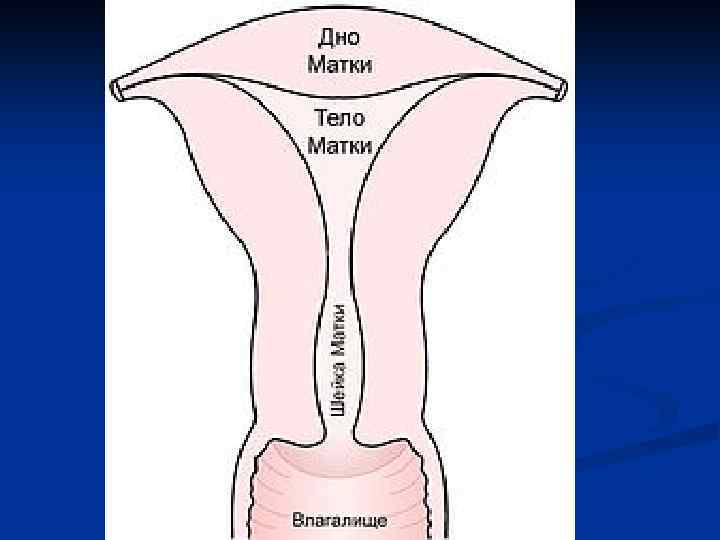

Женские половые органы, organa genitalia feminina

Женские половые органы, organa genitalia feminina

Рис 1 (норма) Гистерограмма: 1 — перешеек матки, 2 — канал шейки матки, 3 — катетер, через который введено рентгеноконтрастное вещество; видно значительное расширение перешейка и канала шейки матки. Рис 2 И стмико-цервика льная недоста точность (insufficientia isthmicocervicalis; Истмико+ анат. cervix uteri шейка матки) -нарушение функции шейки и перешейка матки, проявляющееся зиянием шейки матки, приводящим к самопроизвольному прерыванию беременности; возникает в результате повреждения миометрия или при нарушении гормональной регуляции.

Рис 1 (норма) Гистерограмма: 1 — перешеек матки, 2 — канал шейки матки, 3 — катетер, через который введено рентгеноконтрастное вещество; видно значительное расширение перешейка и канала шейки матки. Рис 2 И стмико-цервика льная недоста точность (insufficientia isthmicocervicalis; Истмико+ анат. cervix uteri шейка матки) -нарушение функции шейки и перешейка матки, проявляющееся зиянием шейки матки, приводящим к самопроизвольному прерыванию беременности; возникает в результате повреждения миометрия или при нарушении гормональной регуляции.